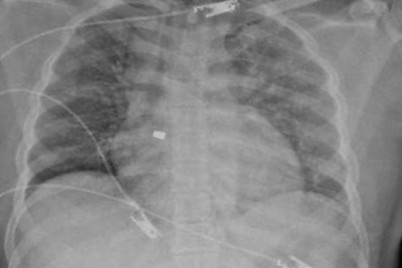

بعد مرور نحو أربع سنوات على بدء جائحة كورونا، لا يزال من الصعب تقييم حالة طالب عمره 12 عاما...